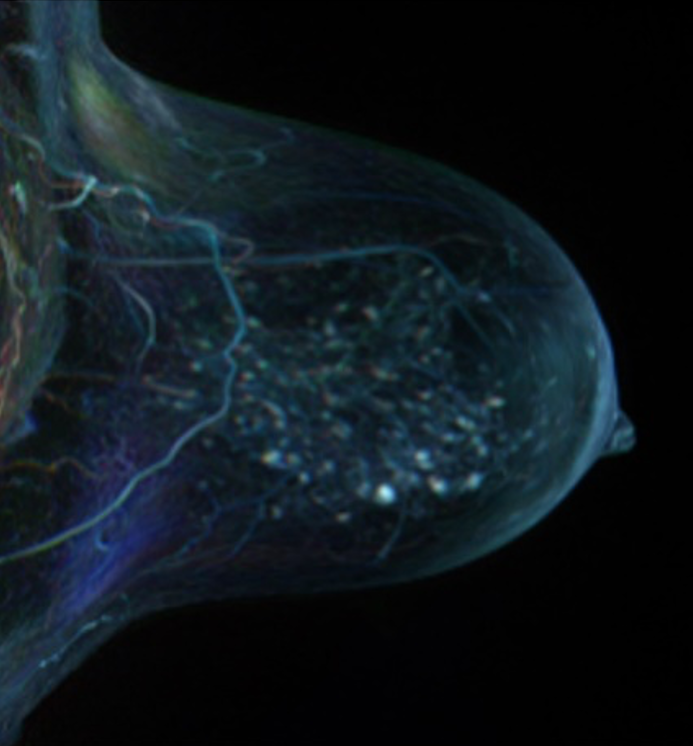

MedUni Wien/© Lorenz Perschy

Image credits: MedUni Wien/Lorenz Perschy